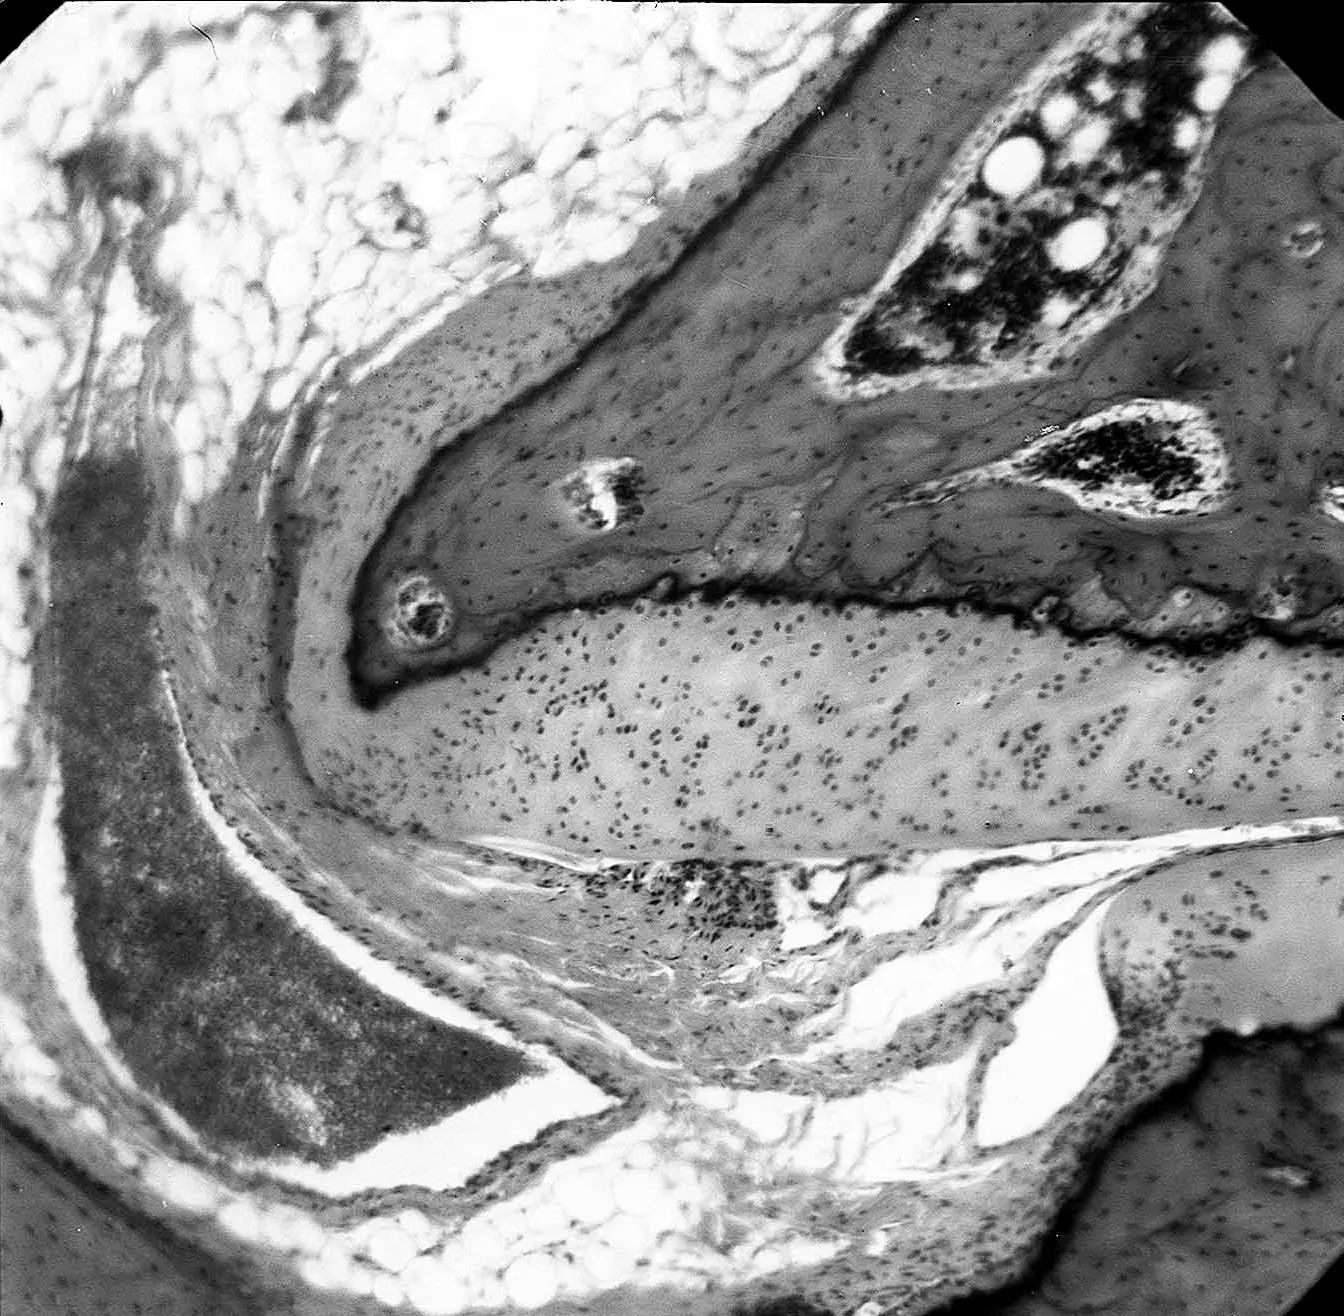

Деформуючий артроз характеризується хронічним порушенням харчування хряща. Страждає також кістка, на якій розташований хрящ. Поступово хрящ зневоднюється, з’являються дефекти хряща, його висота знижується. На рентгені стає видно, як звужується суглобова щілина (на МРТ цього можна і не помітити). Втягується в процес кістка під хрящем, формуються кісткові розростання (Кразанн на мікрофотографії нижче: витончення суглобового хряща, суглобового відростка і формування остеофита при дислокаційному перевантаженні суглоба хребта (формування остеоартрозу).

Результати власних оригінальних експериментів на суглобах хребта: Гонгальский В.В. Ранні сегментарні неврологічні прояви остеохондрозу грудного відділу хребтового стовпа // Автореферат дисертації на здобуття наукового ступеня кандидата медичних наук. 1990.-18с.